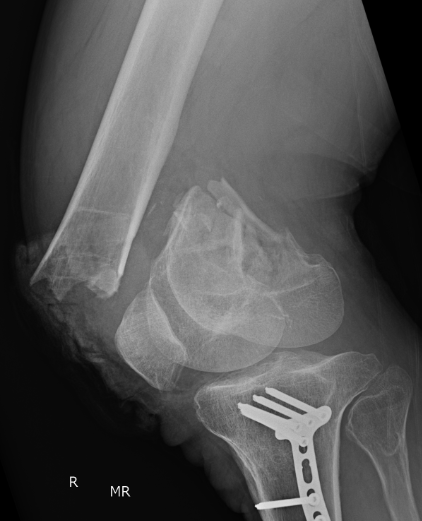

Xray

AO Type B1 & B2: Partial articular

![]()

Definition

Medial or lateral sagittal split